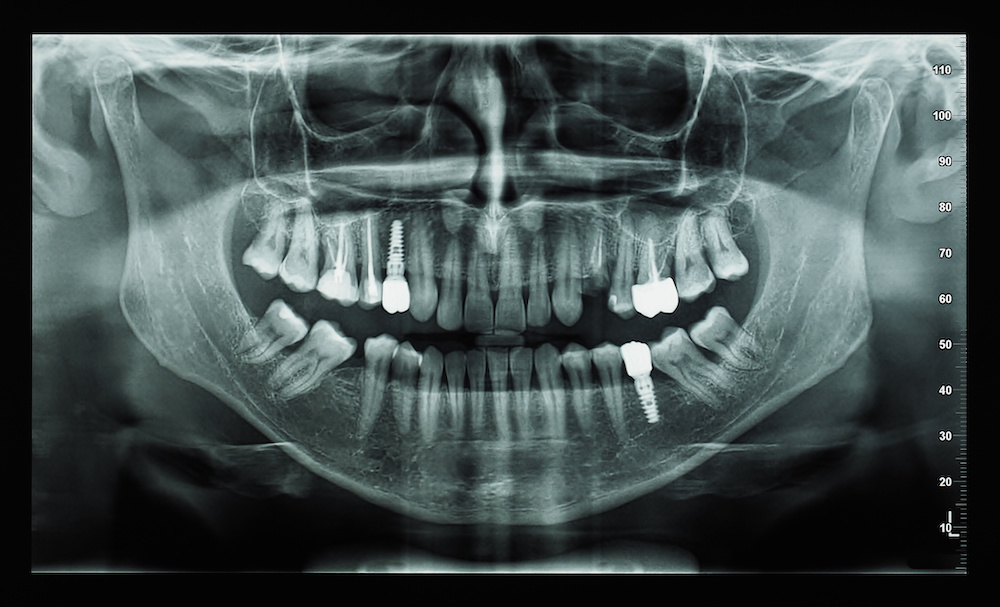

Artificial intelligence has the potential to offer clinicians reliable automated evaluations of bone quality and quantity when planning dental implants, according to a review published in the Journal of Dentistry.

The review included 11 studies involving AI-based assessments of bone quality and/or quantity based on radiographic images in the preoperative phase. The AI models demonstrated high accuracy, high sensitivity and high specificity.